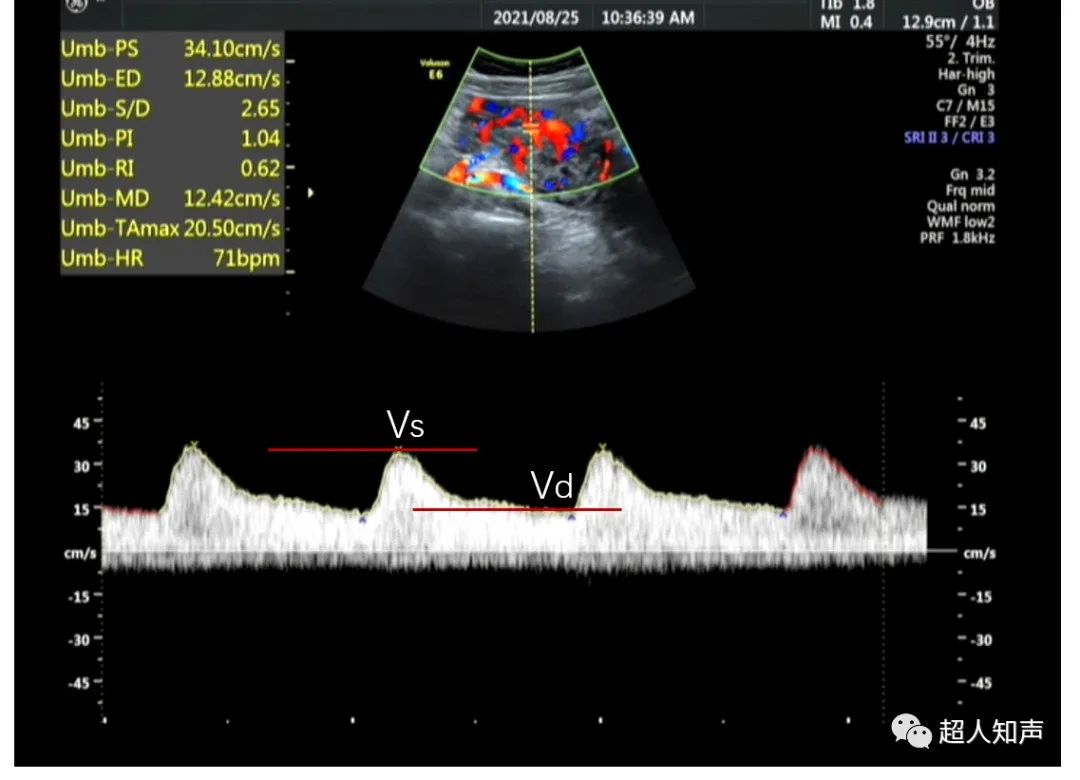

5.“收缩峰”指在心动周期内达到的收缩峰频率,即峰值流速Vs或Vp。

6.“舒张期末”指即将要进入下一个收缩期的舒张期最末点,此点为舒张末期流速Vd。

1.可直接测量出Vs和Vd。(如上图:PSV和EDV)

3.收缩舒张比值:S/D=Vs/Vd

5.阻力指数RI=(Vs-Vd)/Vs

6.搏动指数PI=(Vs-Vd)/Vm